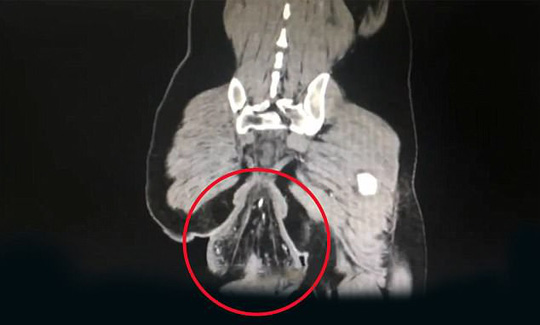

Hình ảnh chụp cắt lớp vi tính (CT) cho thấy phần ruột lòi ra ngoài hậu môn có hình quả bóng với đường kính 16 cm.

Tại bệnh viện, các bác sĩ cho biết phần dị vật có hình dạng khối u này chính là trực tràng đã mất sự gắn kết với cơ thể nhưng vẫn còn bám vào hậu môn.